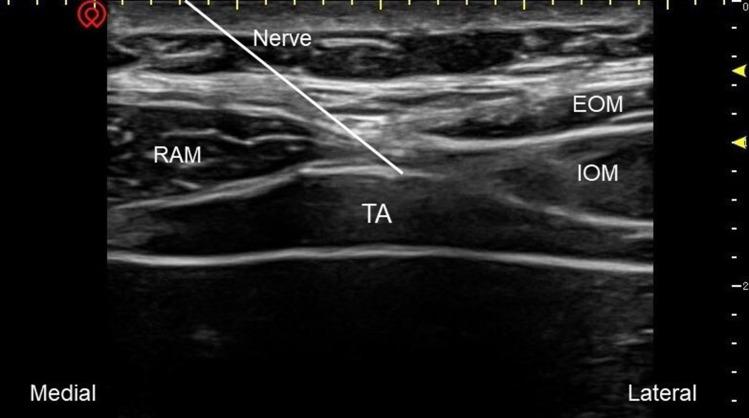

Sixty-two patients undergoing open hepatectomy were enrolled and randomly allocated into the QLB-LSAL group (group Q) and the subcostal TAPB group (group T). Preoperatively, patients received ultrasound-guided bilateral QLB-LSAL or subcostal TAPB with injection of 0.5% ropivacaine (a total volume of 40 mL). The primary outcome was cumulative total morphine equivalent consumption in the first postoperative 24 h. Other outcomes included numerical rating scale (NRS) scores at rest and coughing, cumulative total morphine equivalent consumption at 2, 6, 12, 48 h, Quality of Recovery-15 (QoR-15) scores, time to first patient-controlled intravenous analgesia (PCIA) request, time to first ambulation and adverse effects.

患者与方法